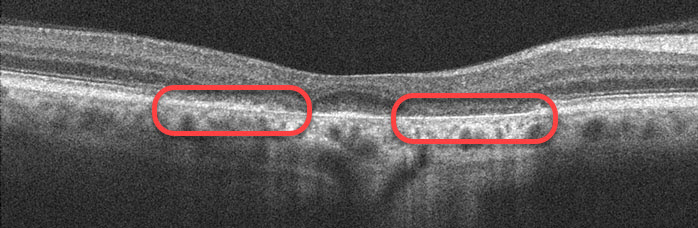

Patients who are receiving Plaquenil need to have a yearly ocular examination (beginning at least within 5 years of starting therapy), including a dilated retinal examination, central visual field testing, and OCT scanning. The drug is usually discontinued at the earliest sign of macular damage since vision loss is usually permanent and can even progress after stopping it.